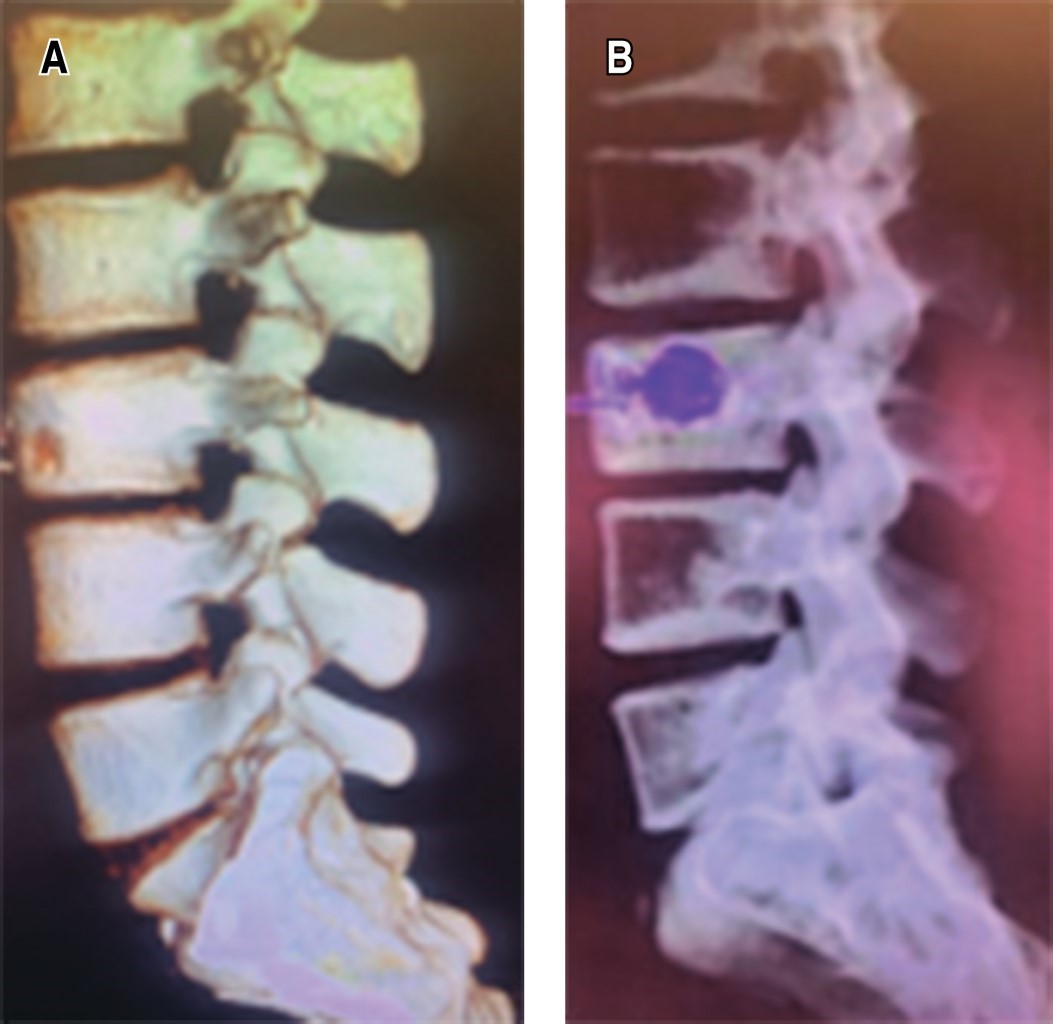

Plan: se decide manejo quirúrgico, cifoplastía L3 + toma de biopsia (Figuras 1 y 2).

El diagnóstico precoz y el tratamiento quirúrgico adecuado del quiste óseo aneurismático en la columna siguen siendo los factores clave para un tratamiento exitoso, y así evitar lesiones neurológicas permanentes.5,13,14 Las opciones de tratamiento son el legrado con o sin injerto óseo, escisión completa, embolización arterial, inyecciones intralesionales de fármacos (esteroides y calcitonina) y radiación.5,6,15 Las tasas de recurrencia después del legrado son igual o menor a 50%.16-18 La regresión espontánea del tumor es poco frecuente.13,19,20 En este particular caso presentado se realizó el manejo quirúrgico mínimamente invasivo con toma de biopsia más cifoplastía dado que el paciente no presentaba lesión adyacente ni inestabilidad de la columna, aunado al tratamiento quirúrgico precoz por esta vía nos aporta prevención a abordajes abiertos y la necesidad de instrumentación de niveles vertebrales adyacentes, lo cual prolonga su estancia hospitalaria y riesgo operatorio, y así obteniendo resultados favorables en el control de los síntomas y recidiva de la enfermedad.7,11,21,22

La edad, la ubicación y el tamaño son sugestivos para la recurrencia y se debe tomar en cuenta el estudio histopatológico para no pasar por alto una neoplasia subyacente más agresiva. El abordaje quirúrgico debe basarse en el conocimiento de la anatomía de la región para lograr la mejor estabilidad y control de la enfermedad. En este sentido complementar con estudios de radiografía dinámica de la columna, así como tomográficos pueden ser de extremada utilidad para la planificación quirúrgica.